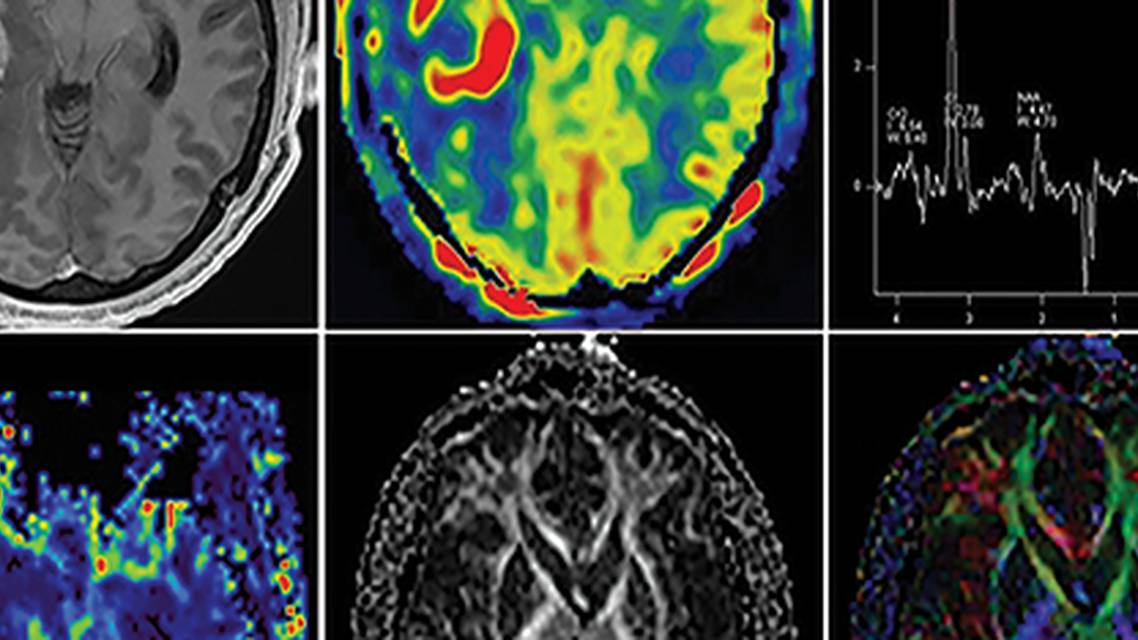

Imaging studies used as a looking glass into the cranium offer a glimpse into the mechanism of AIWS. MRI case reports show visual and auditory hallucinations (both of which are hallmarks of AIWS) can occur in vascular malformations in the right temporoparietal region. Using single-photon emission CT (SPECT) to observe oxygenation perfusion in people with acute AIWS, abnormal blood flow localized to the temporal, occipital, and adjacent perisylvian fissure, all of which are involved in the visual pathway and the visual cortices, was seen.8 In another study, functional MRI (fMRI) was used to observe a boy, age 12 years, experiencing micropsia; increased activation in parietal lobe cortical regions was observed, with reduced activation in primary visual and extrastriatal cortical regions the latter of which are known to be used in the perception of human body parts.9 In most imaging studies of AIWS, symptoms are localized to the temporoparietal junction and occipital visual pathways.